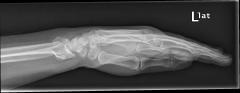

Κατάγματα κάτω πέρατος κερκίδος – κατάγματα Colle’s

Είναι τα συχνότερα κατάγματα στον σκελετό και συμβαίνουν συνήθως σε γυναίκες μετά την εμμηνόπαυση, όταν πέφτουν στο έδαφος και προσπαθούν με συγκρατηθούν βάζοντας την παλάμη. Τα πιο δύσκολα να αντιμετωπιστούν είναι εκείνα που επεκτείνονται μέχρι την αρθρική επιφάνεια.

Περίπτωση 2ου ασθενούς